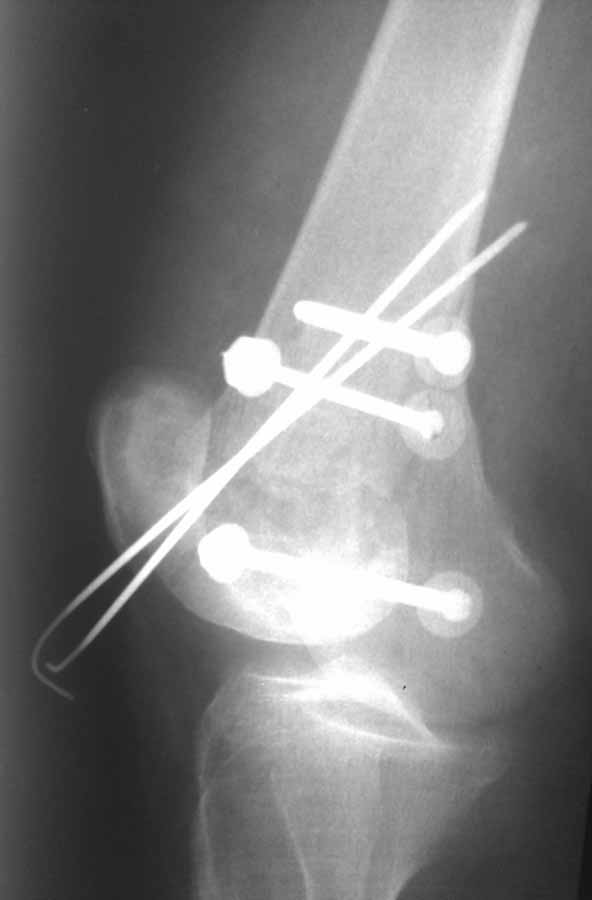

В приложении пример недавней операции, C3, открытая репозиция, фиксация мыщелков спицами и винтами, ретроградный синтез большеберцовым гвоздем 10,5 мм диаметром, винты 5 мм.

По прямому снимку репозиция удалось, поздравляю! А с латеральной стороны подозрение на флексионный компонент латерального мыщелка остается, а снимок получился косым, надо было бы повторить.

Выбор имплантов не совсем удачный, подкожно выступающие болты в мыщелках вскоре могут привести к проблемам. Вместо солитарной фиксации болтом-стяжкой дистально можно было бы добавить пару винтов, которые создали бы ротационную стабильность и межфрагментарную компрессию.